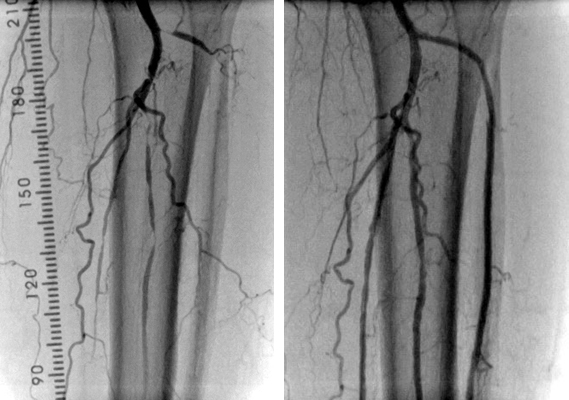

- 大動脈狭窄 【写真】

- 高位大動脈閉塞(Leriche synd) 【写真】

- 腸骨動脈完全閉塞(右) 【写真】

- 腸骨動脈狭窄 【写真】

- 浅大腿動脈狭窄 【写真】

- 浅大腿動脈閉塞 【写真】

- 3枝閉塞 【写真】

- 脛骨腓骨動脈幹(peroneal trunk) 【写真】

- 後脛骨動脈(posterior tibial artery) 【写真】

- 腎動脈 【写真】

- 鎖骨下動脈 【写真】

考え方としては、早期であるほど2の血管内手術のみで治る可能性が高いと考えてよいでしょう。現在の末梢動脈に対する血管内手術の適応は、大動脈・腸骨動脈領域から膝下動脈、さらに足関節から足趾にまで及びます。しかし、それぞれの治療法には当然ながら適応があります。このためしばしば従来からの手術との組み合わせであるハイブリッド手術が必要になりますが、血管内呪術の関与する割合は8~9割にも及んでいます。